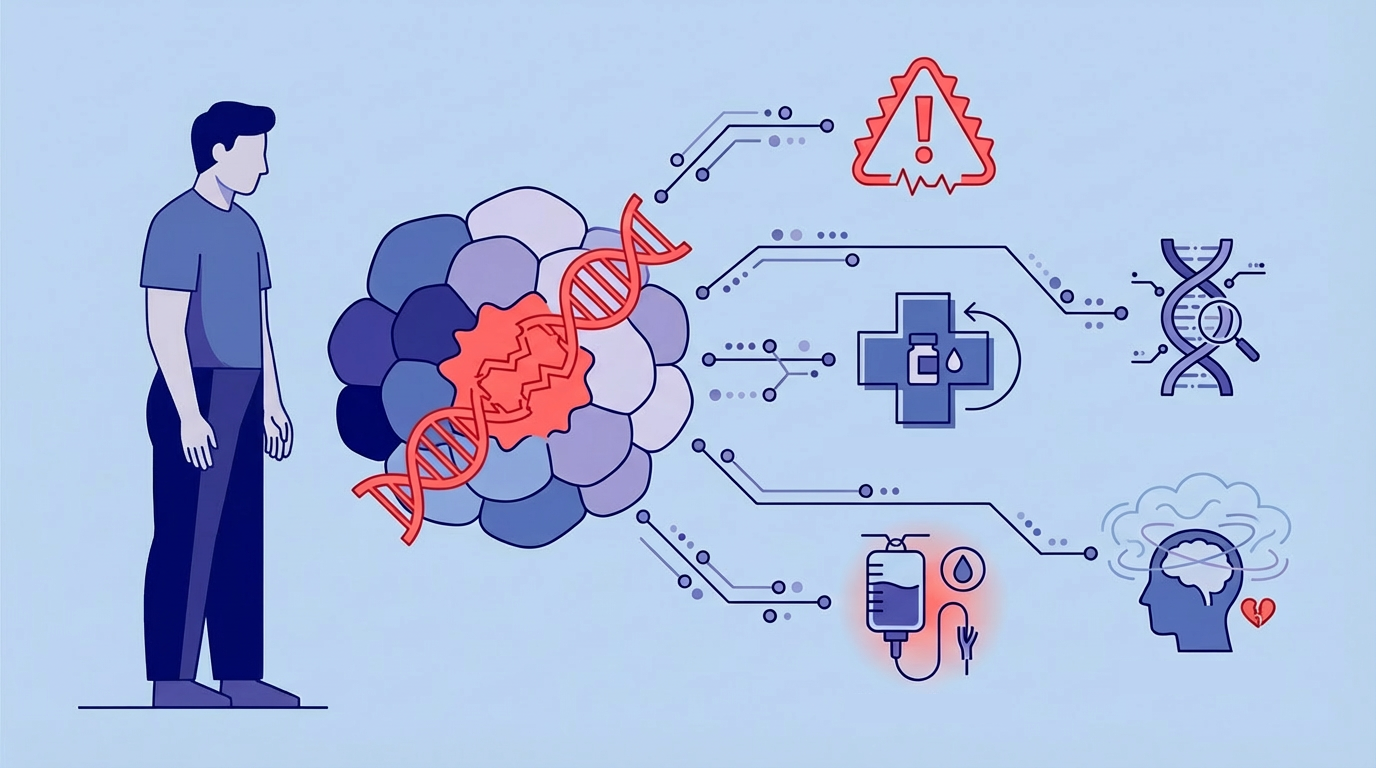

The Sensor-S study demonstrates how data from sensors, wearables, continuous glucose monitors (CGMs), and patient-reported outcome measures (PROMs) can be integrated within a scalable digital research infrastructure. The result is a blueprint for data-driven, patient-centered rehabilitation—developed using D4L Collect.